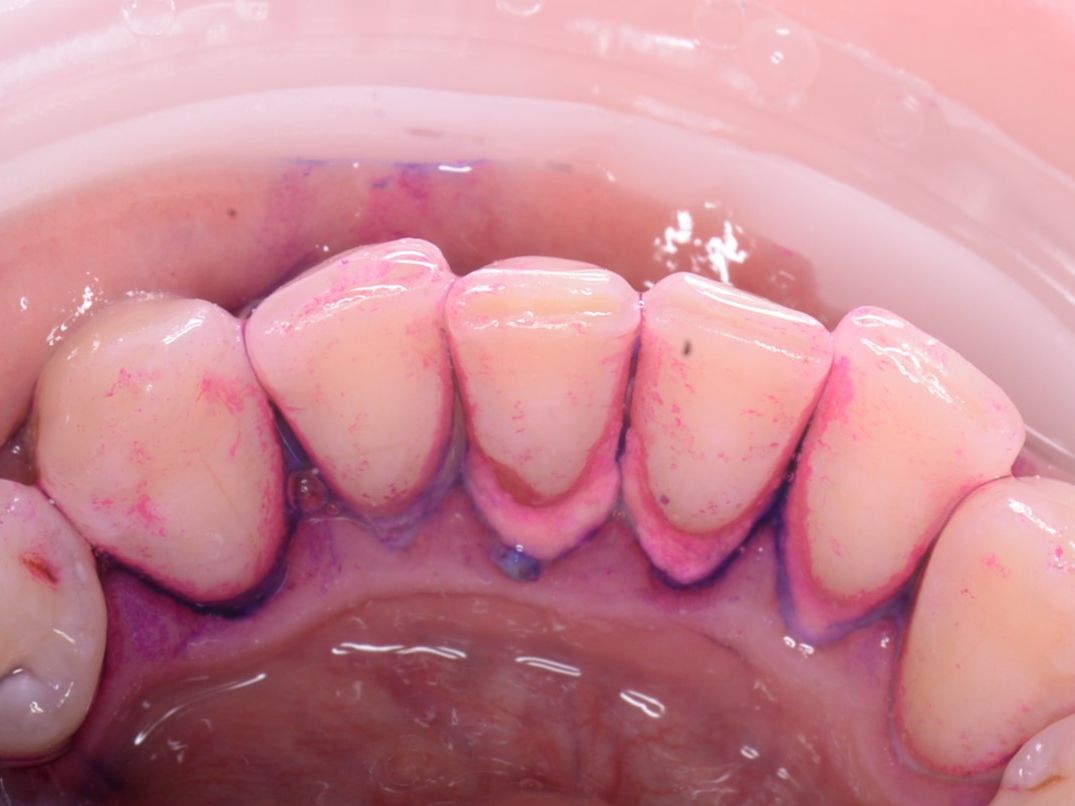

• Профессиональной гигиеной полости рта, включая снятие зубного камня и пигментированного налёта с использованием современного оборудования.